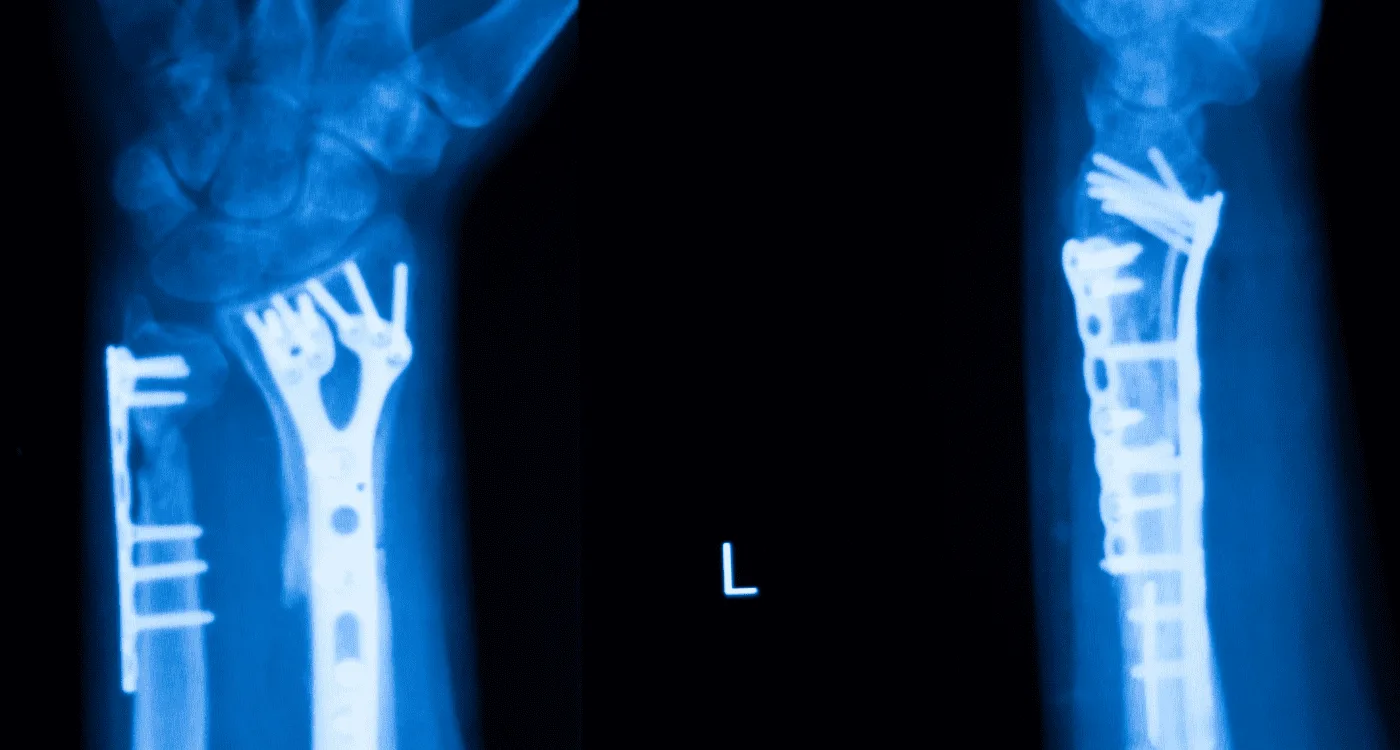

Muchas veces, el dolor articular es el resultado de lesiones traumáticas previas que no sanaron correctamente, como fracturas o luxaciones que alteraron la biomecánica de la zona. En otros casos, el paciente experimenta una rigidez articular progresiva vinculada al desgaste articular o a la artrosis, donde el cartílago pierde su capacidad de amortiguación. Es vital diferenciar estas condiciones de cuadros inflamatorios agudos como la tendinitis o la bursitis, que suelen responder a protocolos de tratamiento distintos pero igualmente especializados.